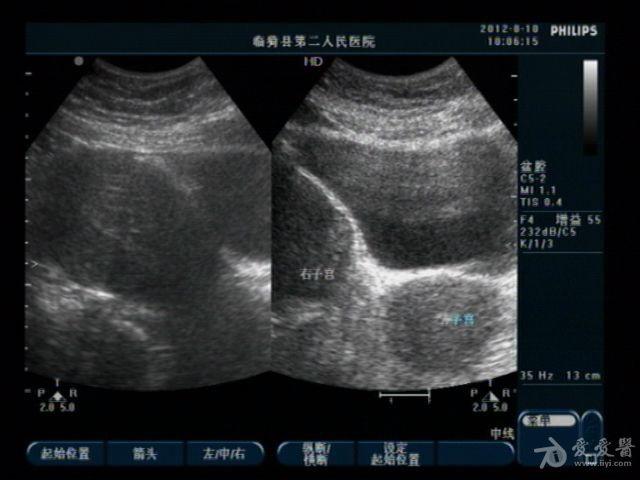

典型双子宫图像

前几天,我们科来了一位老病号,一年前剖腹产患者。当时手术证实“双子宫”今天超声图像可见一大一小两个子宫,右侧较大拟诊“子宫内膜异位症”。患者有经期腹痛史。

患者今年29岁,现生有一孩,就是剖宫产那个孩子。具体是那个子宫患者也不清楚,因在外地做的手术我们未能得到准确资料。患者近几个月来有明显的痛经史